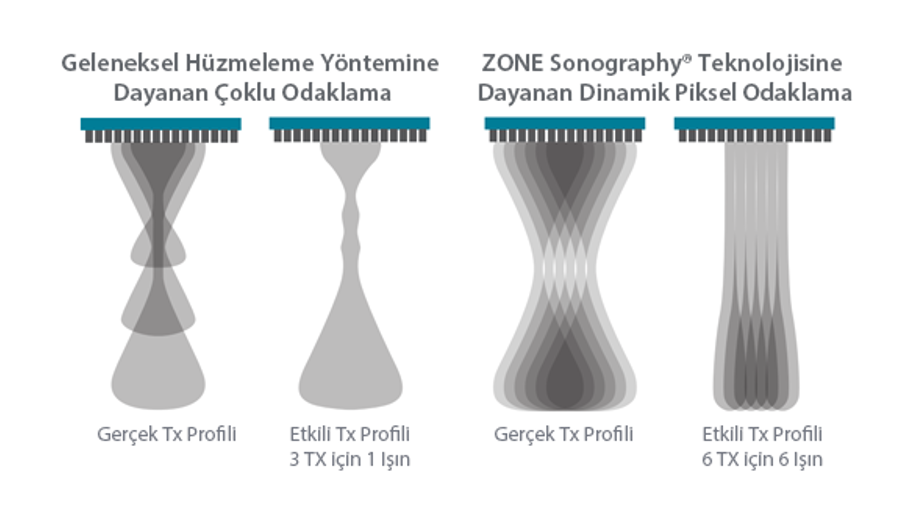

Mindray, ?irketin kuruldu?u gĂŒnden bu yana sĂŒrekli olarak tan?sal do?rulu?u iyile?tirmeye ?al??maktad?r. Devrim niteli?indeki ZONE Sonography? Teknolojisi ile desteklenen Resona 7ânin yeni ZST+ platformu, b?lge g?rĂŒntĂŒsĂŒ alma ve kanal veri i?leme ?zellikleri ile ultrason g?rĂŒntĂŒsĂŒ kalitesini daha ĂŒst bir dĂŒzeye ??kar?yor.